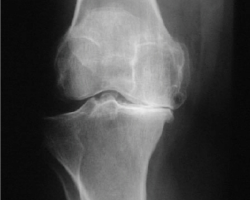

L’arthrose du genou ou gonarthrose (« gono » signifiant genou en grec) est la plus fréquente. Selon une étude américaine, la gonarthrose touche 0.24 % des personnes par année, avec une incidence nettement plus importante au dessus de 70 à 80 ans. (1% chez la femme et 0.8% chez l’homme).